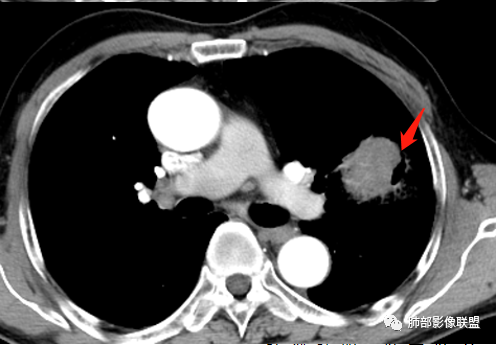

这三个月后的

发了后面这个,就不用纠结了,直接秒了。

大雄:

我只是要告诉大家,不是二元,就是肿瘤,没有什么感染,磨玻璃都没消失。

坏死不是鳞癌多见吗,病理是腺癌。

腺癌也可以的,这个是低分化,恶性程度高,

低分化腺癌坏死常见,转移的淋巴结坏死也常见,这个奇怪的就是淋巴结没有转移,如果有淋巴结肿大,应该会更容易想到低分化腺癌。

反思,恶性膨隆,远端空洞,强化坏死不均,里面血管似乎也是增粗,边界不清,似乎有侵犯。坏死还是边界不清。